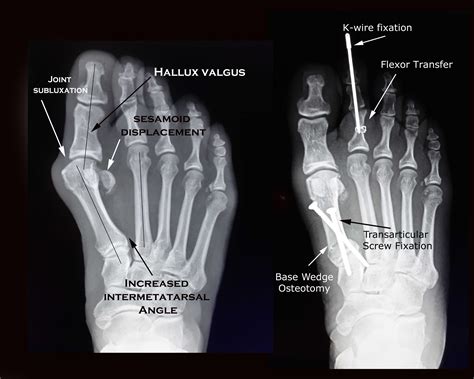

A bunion, medically known as hallux valgus, is a bony bump that forms on the joint at the base of the big toe. Over time, the joint becomes misaligned, causing the big toe to lean toward the second toe. Surgery aims to realign the bone, ligaments, tendons, and nerves to bring the toe back to its correct position. The primary goals are to alleviate chronic pain and correct the deformity to prevent further progression.

1. Osteotomy

Osteotomy is the most common category of bunion surgery. During this procedure, the surgeon cuts the bone of the big toe or the metatarsal bone (the long bone in the foot leading to the toe) and shifts it into the correct position. The bone is then held in place with specialized screws, wires, or plates while it heals.

3. Arthrodesis (Joint Fusion)

For patients with severe arthritis or very large, complex deformities, arthrodesis may be necessary. This involves removing the damaged cartilage from the joint and fusing the bones together with metal hardware. While this effectively eliminates pain, it does result in a loss of motion in that specific joint.

The Lapidus procedure is a form of fusion that targets the joint located further back in the midfoot (the tarsometatarsal joint). By fusing this joint, the surgeon can correct the entire alignment of the metatarsal bone, which is often more effective for preventing recurrence in patients with hypermobile joints.

5. Soft Tissue Procedures

Often, the ligaments and tendons around the toe joint have become stretched or contracted. A soft tissue procedure involves tightening the loose ligaments on one side of the toe and loosening the tight ligaments on the other side to pull the toe back into a straight alignment.

Selecting the right operation is a collaborative decision between you and your podiatric or orthopedic surgeon. Your surgeon will take X-rays to assess the degree of the angle of your big toe (hallux valgus angle) and the angle between the first and second metatarsals. They will explain which technique offers the highest probability of long-term correction based on these measurements. Do not hesitate to ask questions about the expected recovery time, potential complications, and what kind of physical limitations you might face in the months following surgery. Investing time in choosing an experienced surgeon and understanding the procedure will significantly improve your chances of returning to a pain-free, active life.